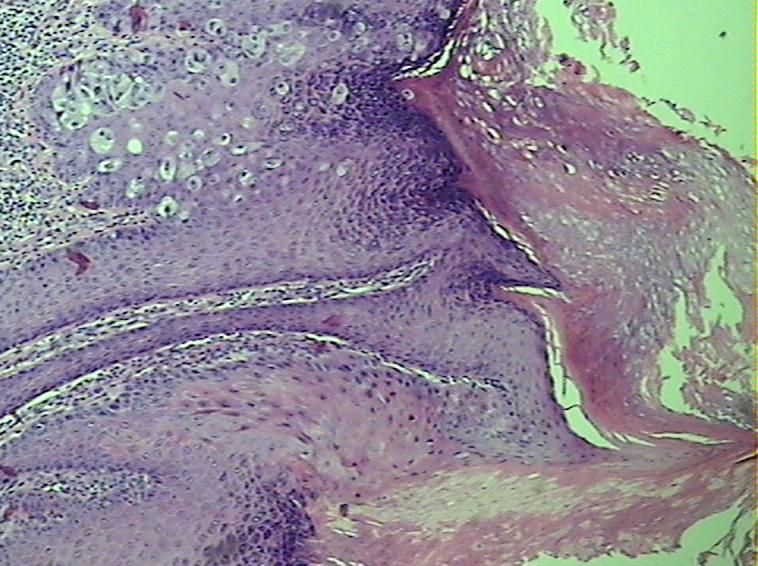

表皮基底及棘层见paget细胞肿瘤细胞胞质透亮,细胞核